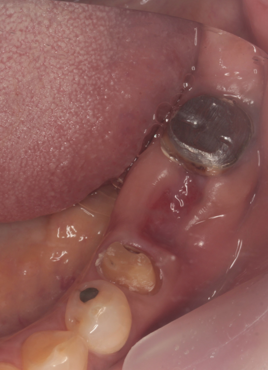

通常抜歯後、顎の骨は吸収する。後のインプラント治療が不利になる。抜歯前の疾患により歯を支える骨を失っており、即時埋入が難しい場合に行っている。

52歳症例